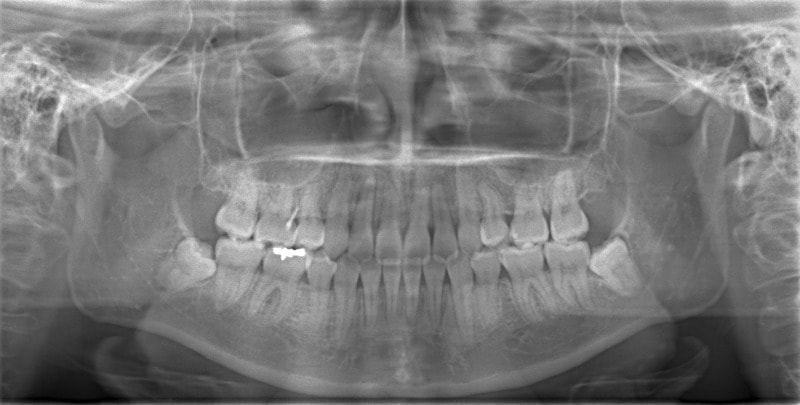

検査時パノラマレントゲン

特に小臼歯部に叢生があり、8番(親知らず)も埋伏しています。8番と7番の接触部分に吸収が若干あるような所見が認められます。

治療中のパノラマレントゲン

歯根吸収もなく、パラレリング(平行性)も確保されております。